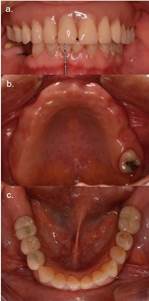

Al instalar la prótesis removible (PR) se pesquisa protrusión labial, línea media superior desviada a la izquierda y un enfilado asimétrico posterior bilateral (Figura 1a, b y c). Debido a esto, se realiza un nuevo enfilado dentario en articulador, sobre una lámina de acrílico de fotocurado para soporte palatino (Profibase®,Voco) y con dientes de acrílico Marché® (Figura 2a y 2b). El enfilado en la zona posterior consta de un premolar y primer molar, para dar contactos posteriores funcionales. Además de corregir parámetros funcionales y estéticos, se confecciona sin flanco para evaluar el soporte labial y perfil facial. Clínicamente se observa una integración facial natural y armónica al agregar exclusivamente dientes (Figura 3).